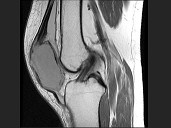

- 单项选择题女,30岁, 膝痛四月余,结合图像, 最可能的诊断是 ( )

A、畸形性骨炎

B、嗜酸肉芽肿

C、成软骨细胞瘤

D、骨囊肿

E、骨巨细胞瘤